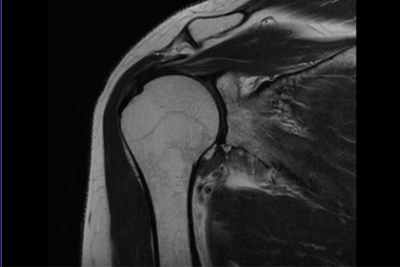

Магнитно-резонансная томограмма, показывающая полный разрыв сухожилия надостной мышцы

Далее в обязательном порядке пациент получает направление на рентген. С помощью рентгенографического исследования врач получает картину, типичную для того или иного случая. К сожалению, именно разрыв не определяется четко, на него могут указать лишь ряд косвенных признаков. Самым информативным методом диагностики на сегодняшний день является магнитно-резонансная томография. С ее помощью можно визуализировать сухожилия, мышцы и связки плечевого сустава. Данный метод предоставляет наиболее четкую и яркую картину состояния мягких тканей пациента.

В случае неясного диагноза и с целью уточнения объема повреждения выполняется ультразвуковое исследование или магнитно-резонансная томография, которая позволяет при помощи магнитных волн увидеть и запечатлеть мягкие ткани и кости в виде послойных срезов.

МРТ плечевого сустава — современный диагностический метод, который дает возможность получить точное трехмерное изображение мягких и костных тканей плечевого пояса. При проведении магнитно-резонансной томографии удается исследовать на патологические отклонения суставов, сосудов, костей, мышц и других тканей плеча.